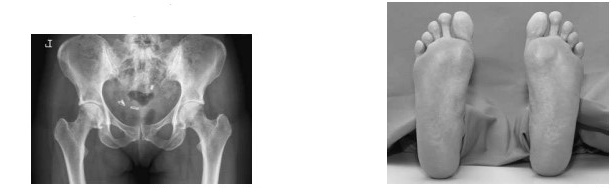

- 외회전(External rotation): 경부와 대전자 부위를 포함한 전위 골절의 경우, 발의 외회전이 발생하며 보통 다리가 짧아지는(단축) 현상이 나타납니다.

하지의 위치와 해부학적 모습

하지의 위치해부학적 소견

| 중립(neutral) | 대퇴골 경부가 비스듬하게 보이며 소전자(lesser trochanter)가 약간 보임 |

| 내회전(Internal rotation) | 대퇴골 경부가 길어져 카세트와 평행하게 위치하며, 소전자는 보이지 않음 |

| 외회전(External rotation) | 대퇴골 경부가 짧아져 있으며 소전자가 뚜렷하게 보임 |

설명과 예시

- 중립(neutral) 상태: 발의 장축이 수직으로 위치하며, 대퇴골 경부가 비스듬히 보이고 소전자가 약간 보입니다.

- 내회전(Internal rotation) 상태: 약 50도 내회전 시, 대퇴골 경부가 길어져 카세트와 평행해지며 소전자는 보이지 않게 됩니다.

- 외회전(External rotation) 상태: 외회전 시, 대퇴골 경부는 짧아지고 소전자가 명확히 보입니다. 이는 전위 골절 시 다리의 외회전과 단축을 설명하는 데 중요한 단서가 됩니다.